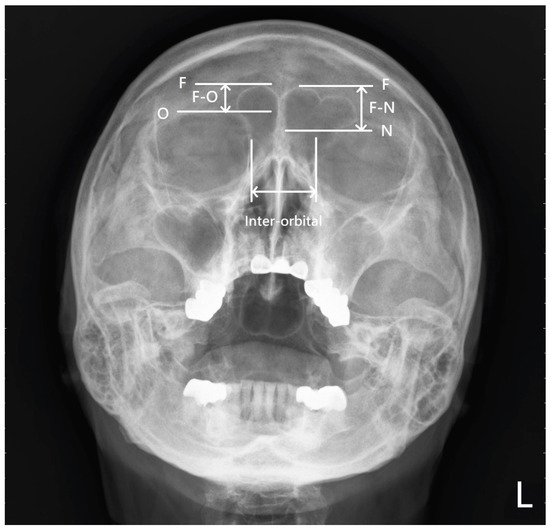

| Types of Frontal Sinus | F-O (mm) | F-N (mm) | Inter-Orbital (mm) | LS-ASB (mm) | |

|---|---|---|---|---|---|

| Normal (n = 107) | Median (IQR) | 18.8 (15.8–21.6) | 23.6 (20.3–27.5) | 28.7 (26.7–30.1) | 17.8 (15.2–20.8) |

| Hypoplasia (n = 91) | Median (IQR) | 12.5 (9.5–15.2) | 17.4 (13.8–20.6) | 26.3 (24.9–28.4) | 14.4 (12.7–16.1) |

| Aplasia (n = 22) | Median (IQR) | 0.0 (0.0–0.0) | 2.4 (0.0–5.8) | 24.9 (23.9–27.8) | 11.0 (9.4–12.9) |

| p value | <0.001 | <0.001 | <0.001 | <0.001 | |